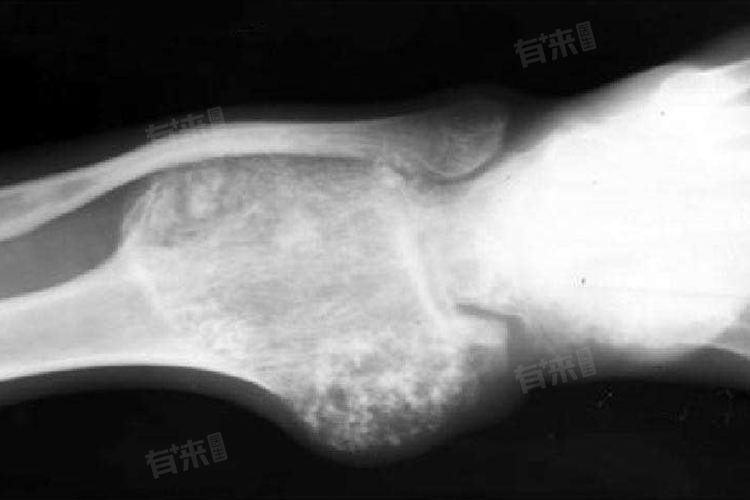

2、肿块:在骨骼表面可触及肿块,质地较硬,边界不清,有时还会伴有局部皮肤温度升高和浅静脉怒张,肿块生长速度通常较快。

4、病理性骨折:骨癌会使骨骼变得脆弱,轻微的外力或日常活动就可能导致骨折,如摔倒、咳嗽等都可能引发骨折,且骨折后愈合困难。